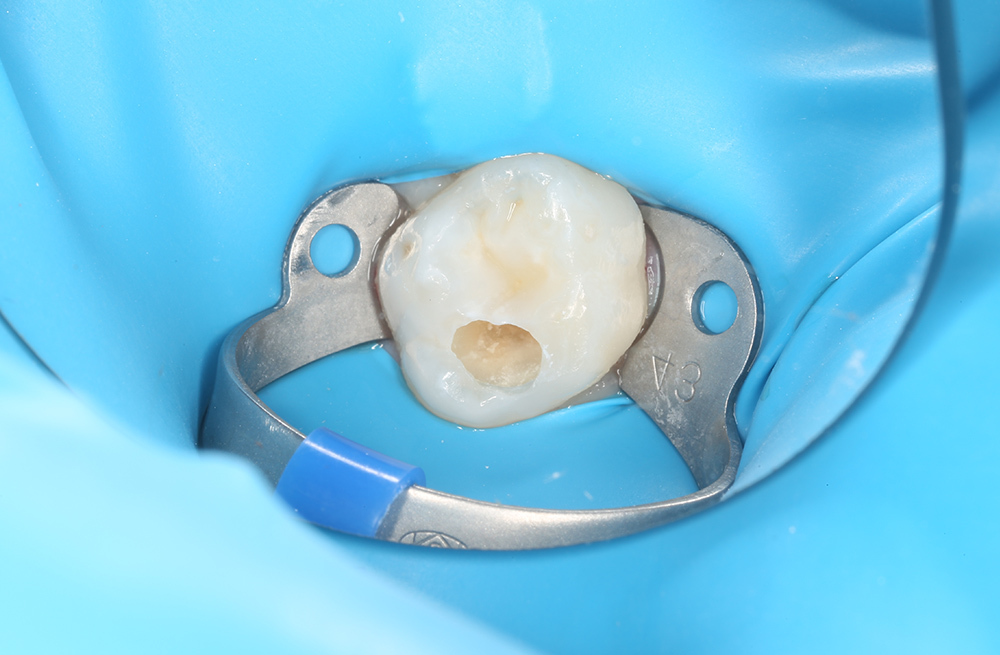

Сохранение зуба при обратимом пульпите